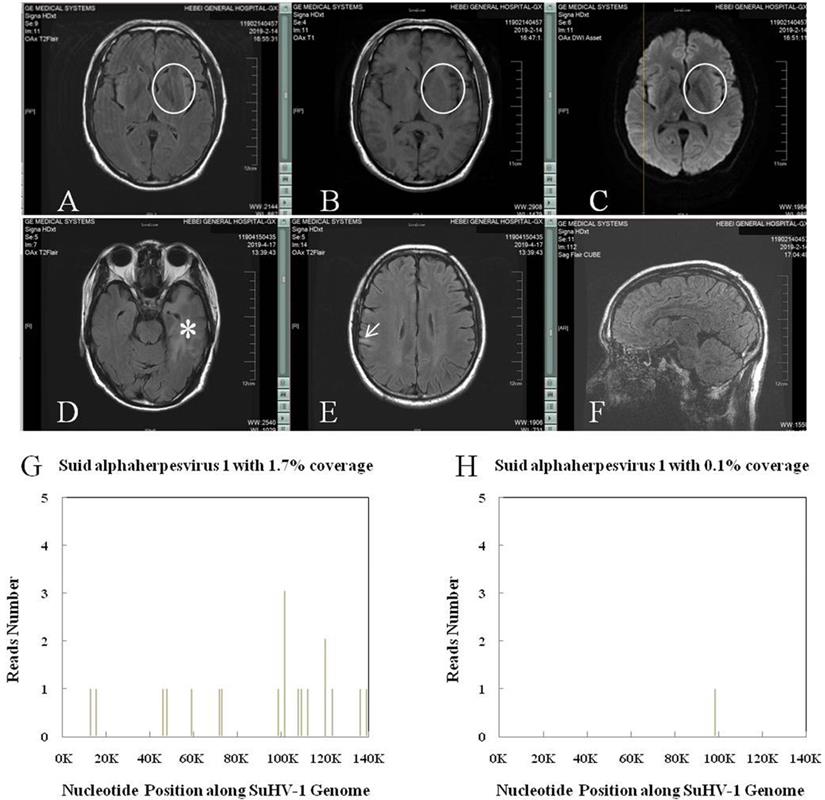

The SuHV-1 encephalitis may produce a high fever and headache, with rapid progression to signs of a CNS infection, including trembling, marked incoordination, altered mental status, seizures and, eventually, coma. Lumbar puncture should be performed early for patients with clinical signs of a CNS infection. Accordingly, the cerebrospinal fluid (CSF) generally showed elevated pressure and results similar to those of other viral encephalitis, accompanied by negative results of tryptophan test, India ink staining, Alixinlan staining and bacterial smear. Neuroimages on the brain magnetic resonance imaging (MRI) usually showed abnormal signals in the limbic system, basal ganglia and brainstem (thalamus) (Figure 4), to which the SuHV-1 had higher affinity [6]. And this might explain the clinical symptoms of altered mental status and frequent seizures. By comparison, abnormal signals in encephalitis caused by herpes simplex virus-1 are usually limited to the limbic system and almost never pass claustrum to involve the basal ganglia and thalamus. Subtle difference in neuroimages can be inferred elsewhere [31]. Nevertheless, next-generation sequencing of the CSF may make the definite diagnosis by identifying unique sequence reads of the SuHV-1 (Figure 4) [32]. Taken together, brain MRI and next-generation sequencing of the CSF should be performed in suspected cases. Management of the SuHV-1 encephalitis should be started expeditiously that included antiviral, human immunoglobulin and symptomatic supportive treatments. In our experience, patients with visual impairment require prompt eye funduscopic examination and glucocorticoids. As a prophylactic measure, education about skin protection of persons under close contact with pigs is necessary to minimize the viral remission.

Figure 4

SuHV-1 encephalitis in patient of chronic kidney disease stage 4 and the high throughput sequencing results. A, B and C: Brain MRI showed intense T2 Flair, T1 and DWI signal changes in the left basal ganglia (circle). D and E: Brain MRI showed intense T2 Flair signal changes in the left hippocampus and temporal lobe (asterisk), and right frontoparietal lobe (arrow), respectively. F: CUBE technique found no sign of meningitis. G: Next-generation sequencing of the cerebrospinal fluid detected SuHV-1 virus with 16 unique sequence reads and 1.7% coverage. H: Next-generation sequencing of the cerebrospinal fluid detected SuHV-1 virus with 1 unique sequence reads and 0.1% coverage 22 days after treatment.